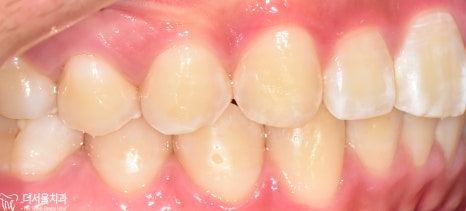

인비절라인 후

구내 사진을 보여드리겠습니다

처음에 보이지 않던

하악 전치부=아래턱 앞니가

이제는 ‘잘’ 보이는 것을 확인해 볼 수 있습니다.

고르지 못했던 치열도

바르게 개선되면서 ‘U’ Shape를 나타냈으며

안쪽 면에 설측 유지 장치를 붙여드리게 되었습니다.

* 치아교정 전

#37번 큰 어금니에 충치가 있던 관계로

인비절라인을 마무리하면서

신경치료 및 크라운을 씌워드렸습니다.*